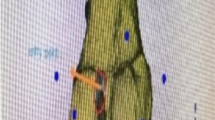

Pre-operative computed tomography (CT) scan of each cadaveric knee was performed using a Discovery PET/CT 690 system (GE Healthcare, USA) with the following characteristics: a minimum slice thickness of 0.625 mm (1 mm max.), contiguous or overlapping slices (no gaps allowed), a matrix size of 512 × 512, a voxel size of 0.6, and an anatomical region default kernel (standard or high resolution) of 90–120 kVp. The images were post-processed to a mesh-volume file, and specific segmentation of the region of interest was performed with Materialise Mimics 21.0 (Mimics Innovation Suite, Materialise MV, Belgium). Mesh-volume files were transferred to the design software 3-matic 13.0 (Mimics Innovation Suite, Materialise MV, Belgium) to conduct surgical planning and surgical guide design. For this purpose, the anatomical femoral attachments of the lateral collateral ligament (LCL) and popliteal tendon (PT) on the lateral side [24] and the medial collateral ligament (MCL) and posterior oblique ligament (POL) on the medial side [25] were first identified. Then, four bone tunnels were planned for each knee starting from the anatomical attachments of the LCL, PT, MCL, and POL applying different directions. Two personalized surgical guides were designed each knee to reproduce the planned tunnels during surgery: the first one for the LCL and PT and the second one for the MCL and POL. The direction of the tunnels was variable. The design criteria to be followed in all cases were as follows: (1) no coalescence of the planned tunnels, (2) no intra-articular invasion at the femorotibial level, and (3) no invasion of the femoral trochlea. This allowed us to analyze the degree of precision of the technique in different surgical scenarios.

Accuracy analysis

Post-operative CT scans were performed of each cadaveric knee, followed by segmentation and the creation of mesh-volume files similar to the pre-operative procedure. The accuracy of the use of 3D-printed PSI was assessed by superimposing post-operative CT mesh-volume files onto pre-operative ones. The entry point deviations of the performed tunnels were analyzed from the planned tunnels, measured in millimeters (mm). Then, the angular deviation was analyzed and measured in degrees. Angular deviation is defined as the angle between the vectors crossing from the centres of the planned and performed tunnels in the x, y, and z planes, as shown in Figs. 4A–B and 5A–D.